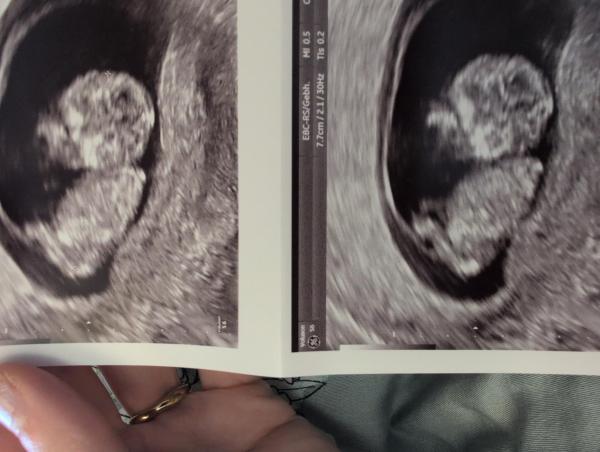

Hallo, kennt sich jemand mit der Nub Theorie aus. Ultraschall ist von heute, ich komme morgen in die 12te Woche. Habe mich ein bisschen eingelesen in die Nub Theorie aber die angewinkelten Beine machen es sehr schwierig 😄 Ich denke, am letzten Bild unten das hinter dem Bein mit der langen Linie weg sollte die Nabelschnur evt. sein oder?  LG Simone

Bild zu Nub - Schwanger - wer noch? Rund um die Schwangerschaft

Ich kann da leider keinen Nub erkennen liebe Simsi 🙆‍♀️